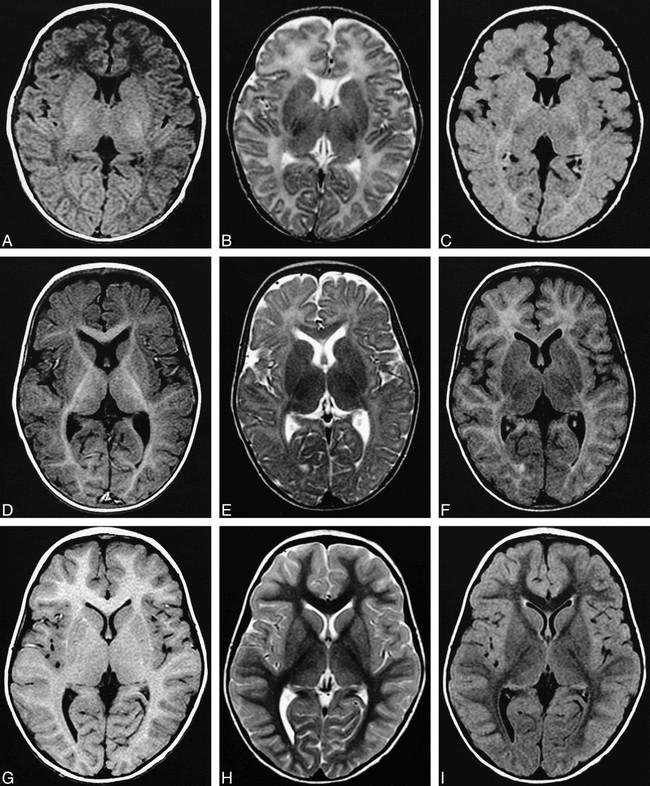

Alobar

Most severe, complete lack of “cleavage”, fused thalami.

Semilobar

“ in between” with separated occipital lobes

Lobar Mild, often only anterior frontal lobe fused, with separate thalami